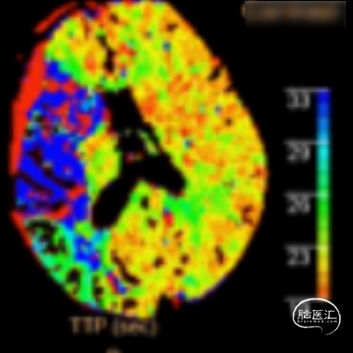

术前CTA+CTP示:1.右侧大脑中动脉M1段闭塞,前交通开放,右侧后交通开放;2.右侧大脑中动脉供血区大面积TTP、MTT延长,CBF降低,CBV减低。